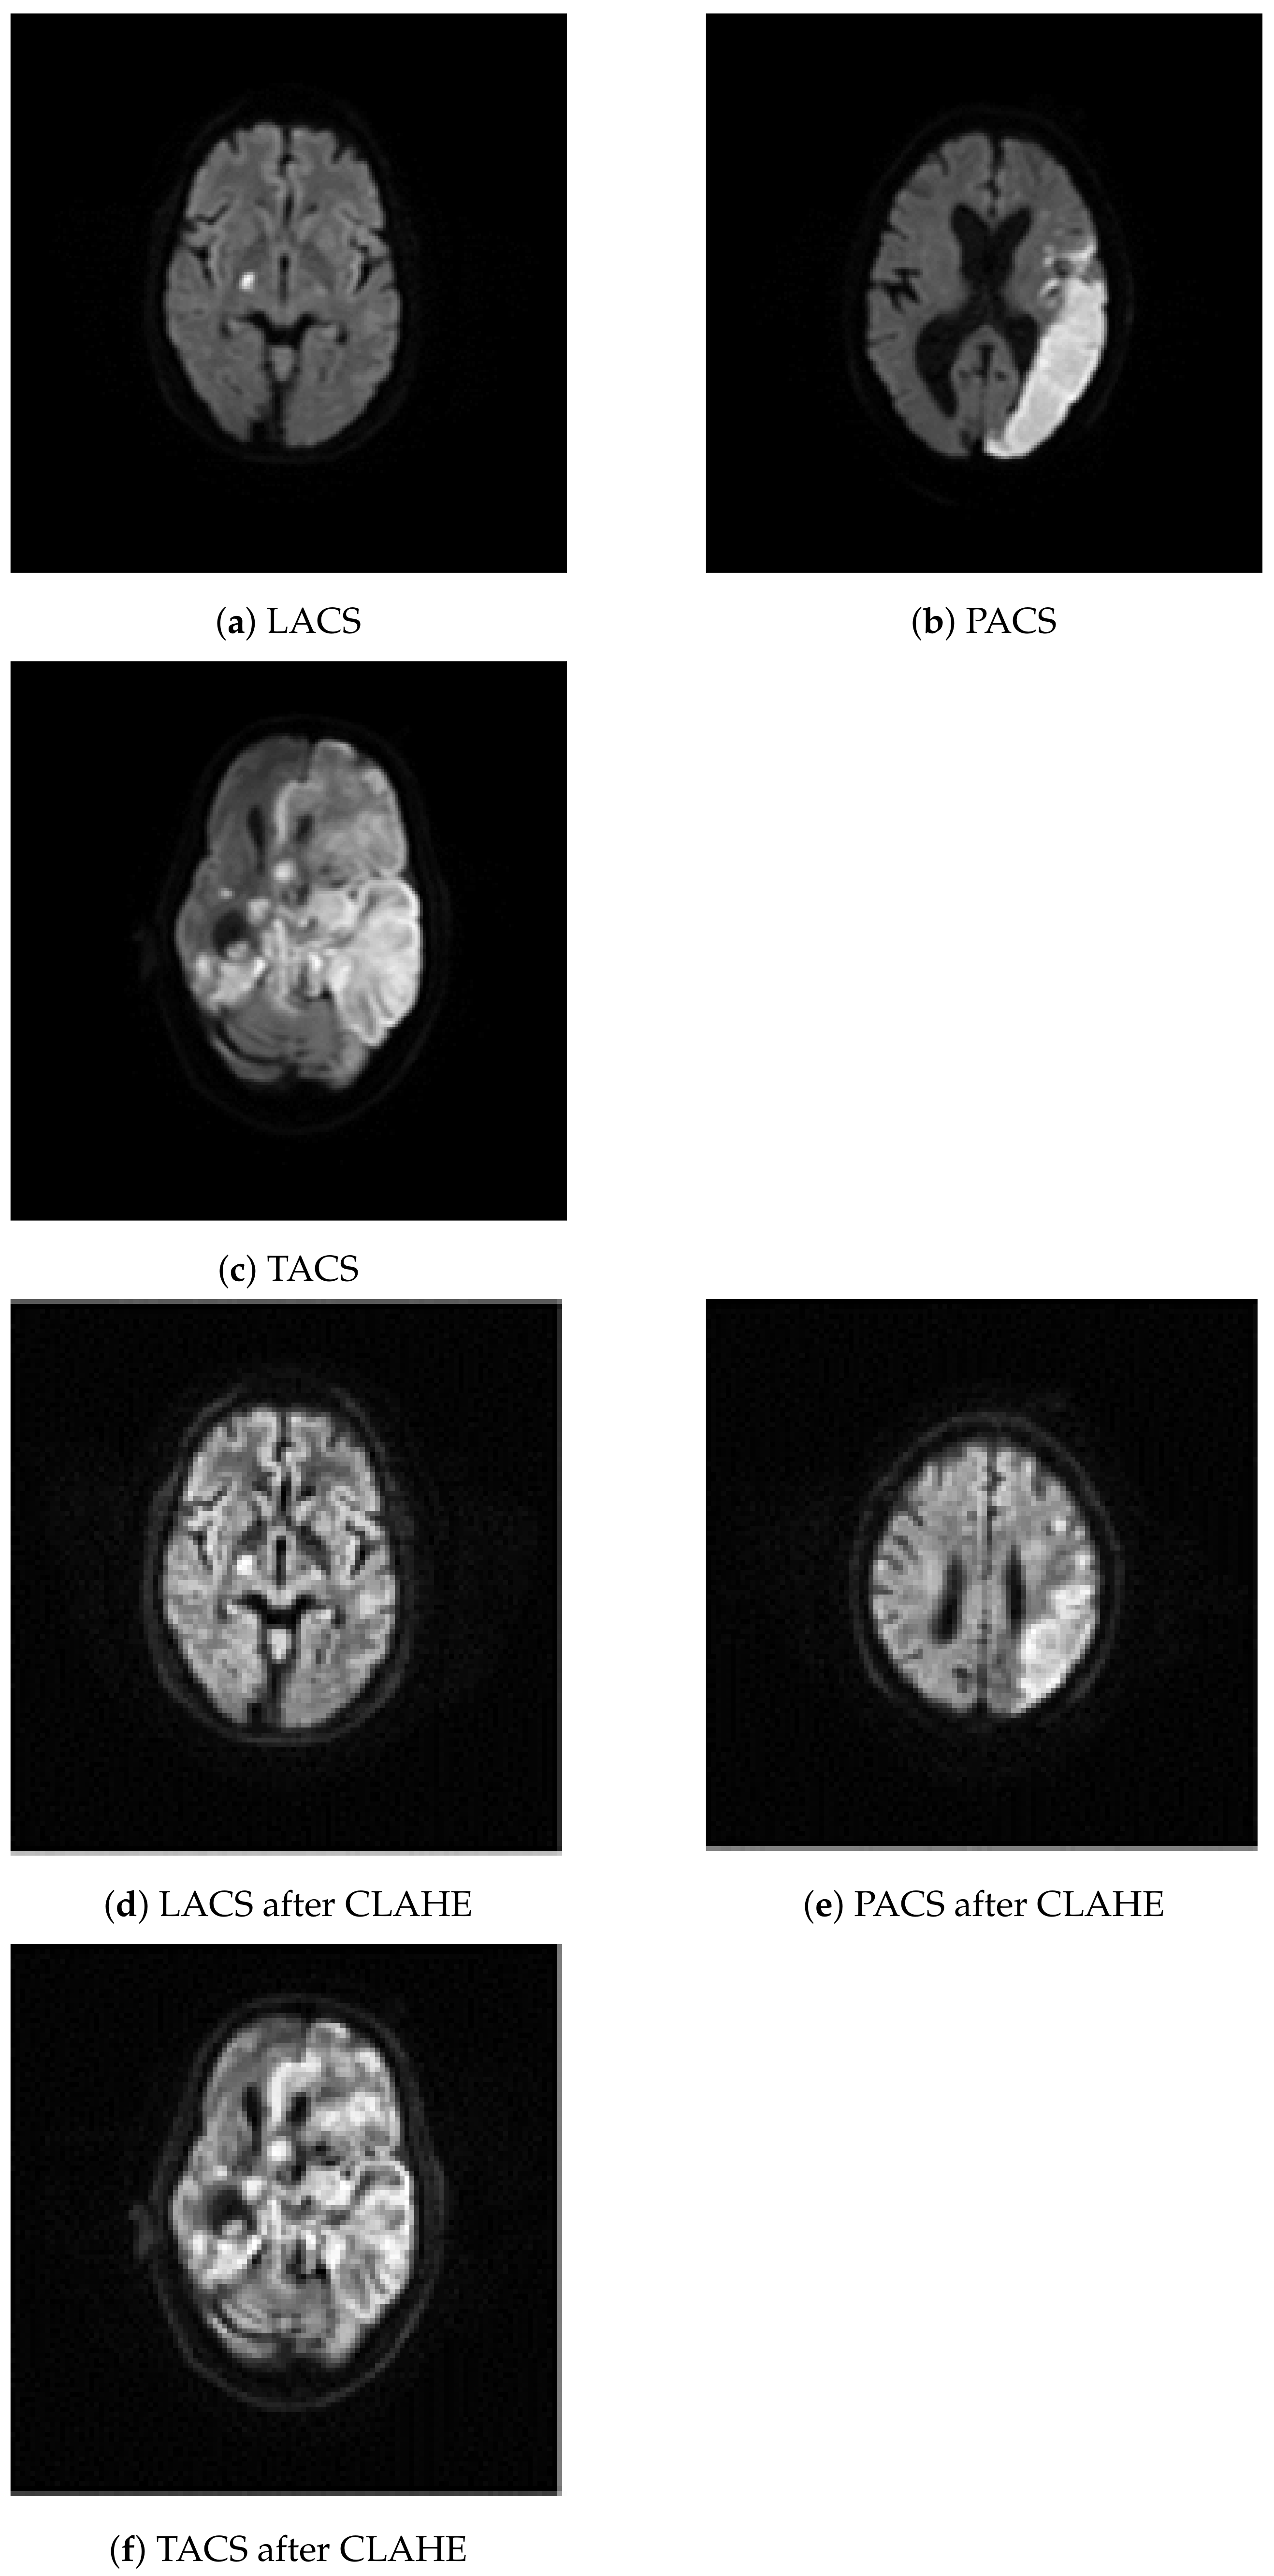

2.2. Image Resizing and Contrast Limited Adaptive Histogram Equalization